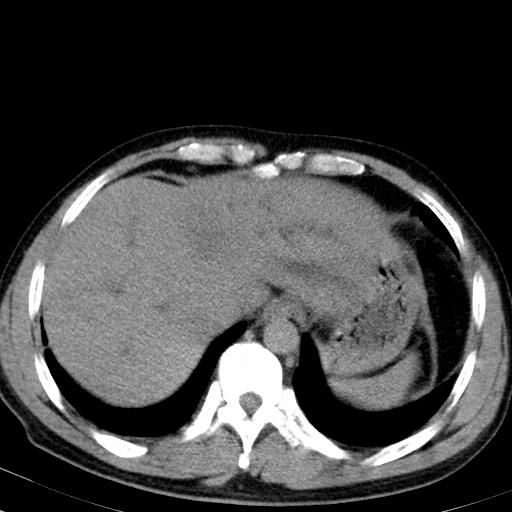

患者上腹部疼痛一月余,伴巩膜黄染;

实事求是的说,强化效果很一般,重点部位应重点观察,但有一点可以明确:肝门部胆管细胞癌。

考虑肝左叶胆管细胞癌侵犯肝门区并肝内胆管及肝总管扩张。

肝左叶肿块清度增强,所在的叶胆管扩张。考虑胆管细胞癌。